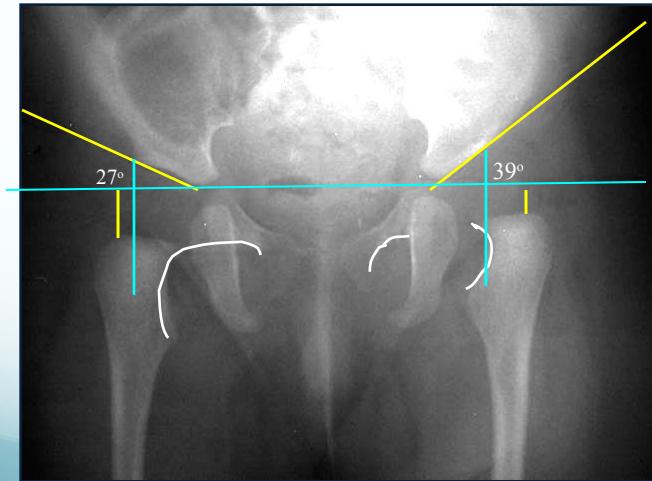

3. Acetabular Index (Acetabular Angle)

- Measurement: Angle from acetabular edge to base at horizontal line

- Normal: ≤ 25°

- Dislocated: > 35°

4. Shenton’s Line

- Important assessment tool for hip joint integrity